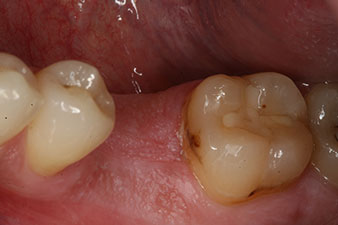

Първи мандибуларен молар при млад пациент трябва да бъде екстрахиран поради тежко увреждане от кариес с ендодонтски усложнения. Поставянето на корона на съседните здрави зъби може да се избегне само с имплант. Шест седмици след екстракция, алвеолите се оказват с недостатъчна кост. Имплантирането трябва да се комбинира с обграждаща аугментация.

28-годишен пациент с анамнеза на тежък пушач е с екстрахиран 36 зъб в резултат на повторяем апикален пародонтит.

Поради почти незасегнатите съседни зъби, единственият начин за запълване на пространството е с имплант.